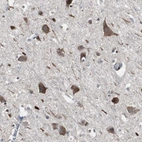

Immunohistochemistry analysis in human liver and pancreas tissues using HPA007244 antibody. Corresponding ACAA1 RNA-seq data are presented for the same tissues.